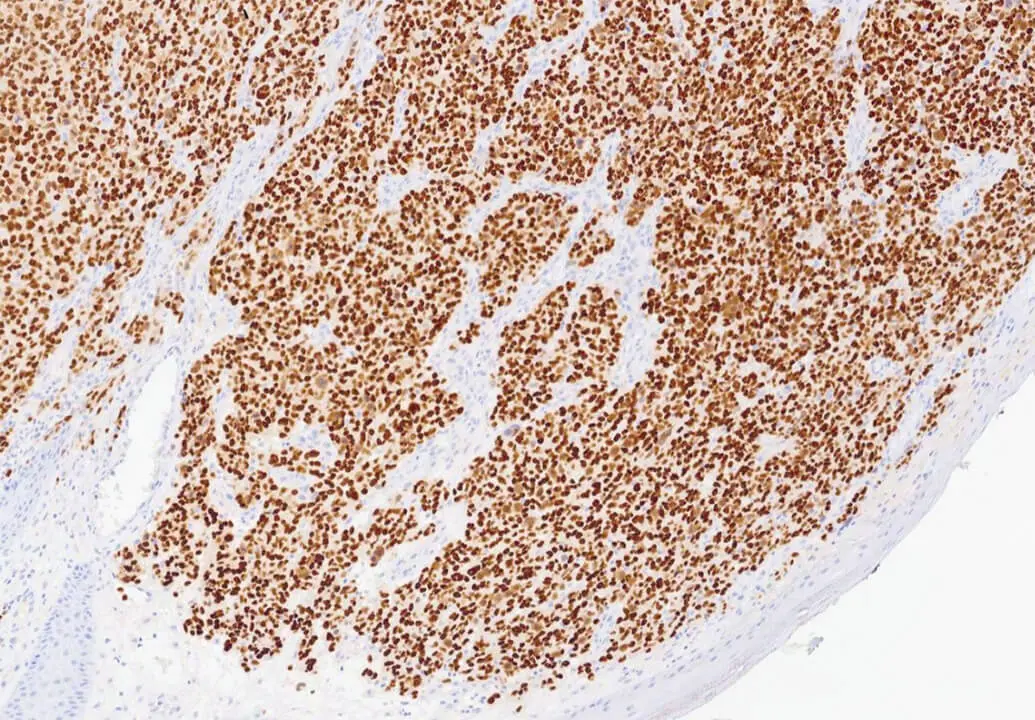

Melanoma: DAB staining of SOX10. Clone SOX10/991.

SOX10 is a nuclear transcription factor in the SOX (SRY Box) family of proteins, that plays an important role in neural crest development among other functions. As such it is expressed in cells of neural crest origin, including melanocytes and Schwann cells. It has been shown to be a sensitive and specific marker to aid in the diagnosis of melanoma, including spindle and desmoplastic subtypes, as well as a specific marker to aid in the differentiation of Malignant Peripheral Nerve Sheath Tumor (MPNST) from synovial sarcoma.